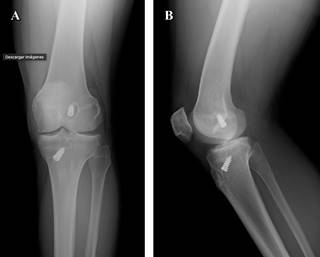

Se empieza abordaje diagnóstico con radiografías convencionales de rodilla derecha en proyecciones anteroposterior y lateral (Figura 1), así como resonancia magnética simple de rodilla para valorar de forma específica estructuras intraarticulares, características de lesiones condrales y del remanente meniscal en el compartimento lateral. Las imágenes de resonancia magnética arrojan los siguientes resultados: injerto de ligamento anterior adelgazado, de aspecto no competente, con disposición vertical e incipiente tejido fibrocicatricial ventral (Figura 2A); cambios en compartimento femorotibial lateral con adelgazamiento condral con zonas de delaminación, fisuras de espesor completo y edema subcondral (Figuras 2B-C); cambios por meniscectomía lateral (Figura 2D); menisco medial con un desgarro oblicuo que muestra apertura a la superficie articular condilar en un corte (Figura 2E).

Figura 1: A) Radiografías anteroposterior y B) lateral a 30o, en las cuales se observan cambios quirúrgicos con tunelización del cruzado anterior con tornillos de fijación, el tornillo colocado en el cóndilo femoral muestra área radiolúcida a su alrededor que sugiere probable aflojamiento. Cambios quirúrgicos a nivel de la tuberosidad anterior de la tibia.